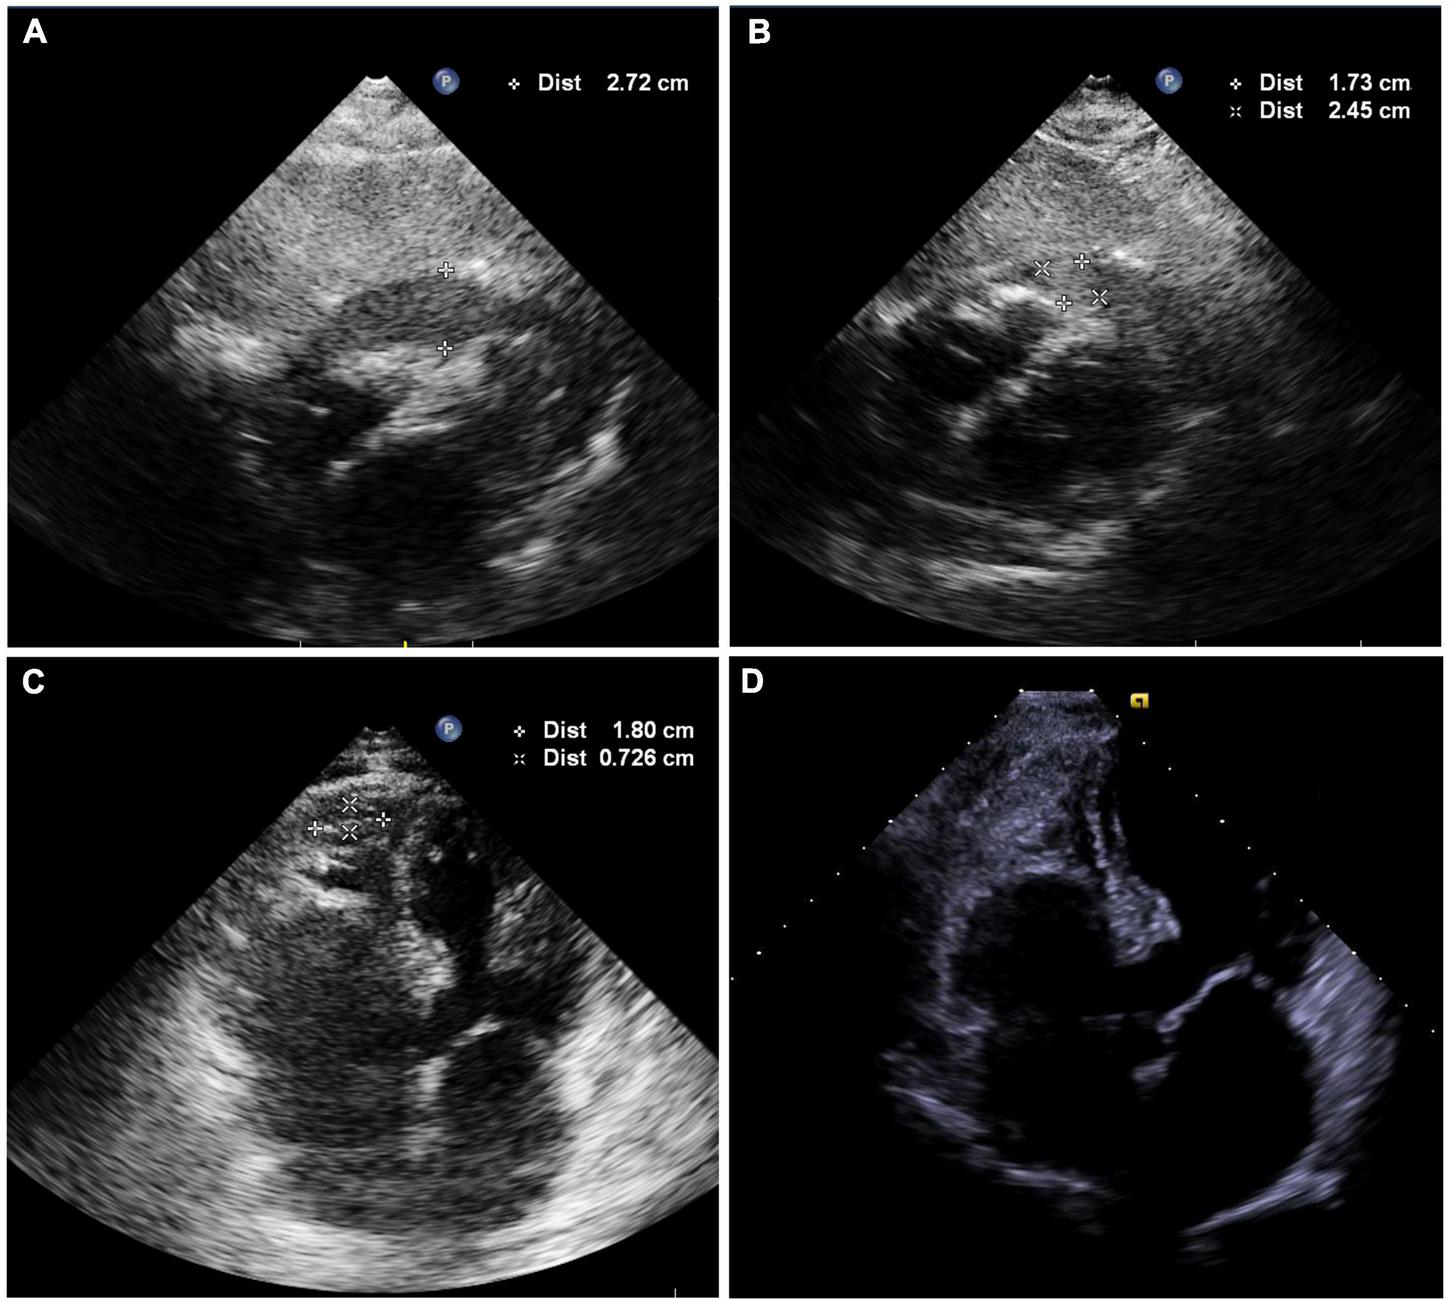

FIGURE 3

(A) Echocardiography showing hypoechoic (rather than anechoic) areas in the pericardial space. (B) Echocardiography shows mild effusions with a round hyperechoic thrombus in the vicinity of the right ventricular apex after intrapericardial thrombus aspiration. (C) Image showing shrinkage of the round thrombus, which appears as a strip in the vicinity of the right ventricular apex on the second postoperative day (Supplementary Video 8). (D) Echocardiography was obtained 2 weeks after discharge and showed no thrombus or pericardial effusion (Supplementary Video 9).

Following 10 min observation, the patient’s heart rate showed intermittent slowing with a decrease in blood pressure to 90/62 mmHg. A temporary pacing lead was placed into the right ventricular to maintain a ventricular rate of > 60 beats per minute. Fluoroscopy revealed a near-normal-sized cardiac silhouette (Figure 2A and Supplementary Video 5), and minimal pericardial blood was drained after the insertion of a new pigtail catheter. The decrease in blood pressure was likely attributable to suspected pericardial thrombosis. Emergency echocardiography revealed a hypoechoic (rather than anechoic) effusion in the pericardial space (Figure 3A), suggestive of early pericardial thrombosis. The emergency surgical team was summoned to prepare for open chest surgery.

The patient’s blood pressure was temporarily stable at approximately 90/60 mmHg; therefore, intrapericardial thrombus aspiration was attempted before surgery. However, thrombus aspiration failed using a pigtail catheter, which was replaced by an 8.5 F long sheath (SL1, Abbott, MN, United States). Unfortunately, thrombus aspiration through the sheath was also unsuccessful. Thereafter, we used a dedicated thrombus aspiration catheter. A 6F guiding catheter (Judkins R4.0, Medtronic, MN, United States) was inserted through the long sheath into the pericardial cavity via an angioplasty guidewire (BMW, 0.036 cm × 190 cm, Abbott, MN, United States), and a thrombus aspiration catheter (Thrombuster II, Kaneka Medical Products, Osaka, Japan) was advanced into the pericardial cavity via the guidewire. Following manipulation of the guiding catheter and guidewire, we could maneuver the thrombus aspiration catheter to successfully aspirate the thrombus from multiple sites across the pericardium (Figures 2B,C and Supplementary Videos 6, 7). Sludge-like blood (instead of a thrombus) was drained using the aspiration catheter (Figure 2D). We aspirated 120 ml of sludge-like blood after 10 min. The patient was hemodynamically stable, and blood pressure returned to 123/62 mmHg. Echocardiography revealed mild effusion and a round hyperechoic thrombus (2.5 cm × 1.7 cm) in the vicinity of the right ventricular apex (Figure 3B). A pigtail catheter was placed to monitor the pericardium, and the patient was transferred back to the ward.

The pigtail catheter was removed on the second postoperative day after echocardiography confirmed the absence of pericardial fluid reaccumulation. We observed shrinkage of the round thrombus, which appeared as a strip that measured 1.8 cm × 0.7 cm in size near the right ventricular apex (Figure 3C and Supplementary Video 8). Anticoagulation was re-initiated on the third postoperative day, and the patient was discharged on the fifth postoperative day. Echocardiography performed 2 weeks after discharge revealed no thrombus or pericardial effusion (Figure 3D and Supplementary Video 9), and the patient had no thromboembolic event or pericardial effusion during 1-year follow-up.